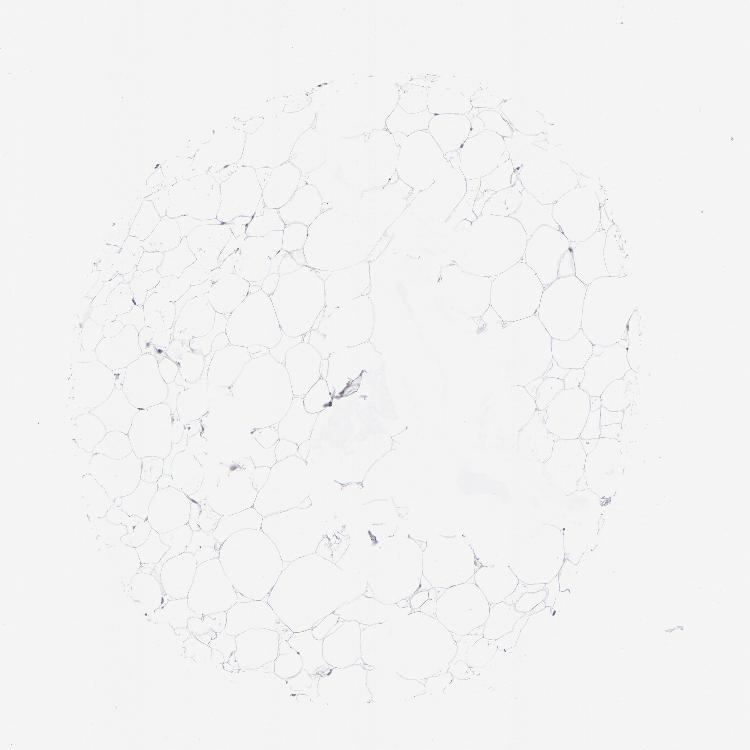

SOFT TISSUE 1 - Antibody stainingi

Antibody staining in the annotated cell types in the current human tissue is reported as not detected, low, medium, or high, based on conventional immunohistochemistry profiling in selected tissues. This score is based on the combination of the staining intensity and fraction of stained cells.

Each image is clickable and will lead to virtual microscopy that enables deeper exploration of all samples and also displays staining intensity scores, fraction scores and subcellular localization as well as patient and tissue information for each sample.

Antibody HPA001923Antibody HPA003908

Fibroblasts Not detectedNot detected